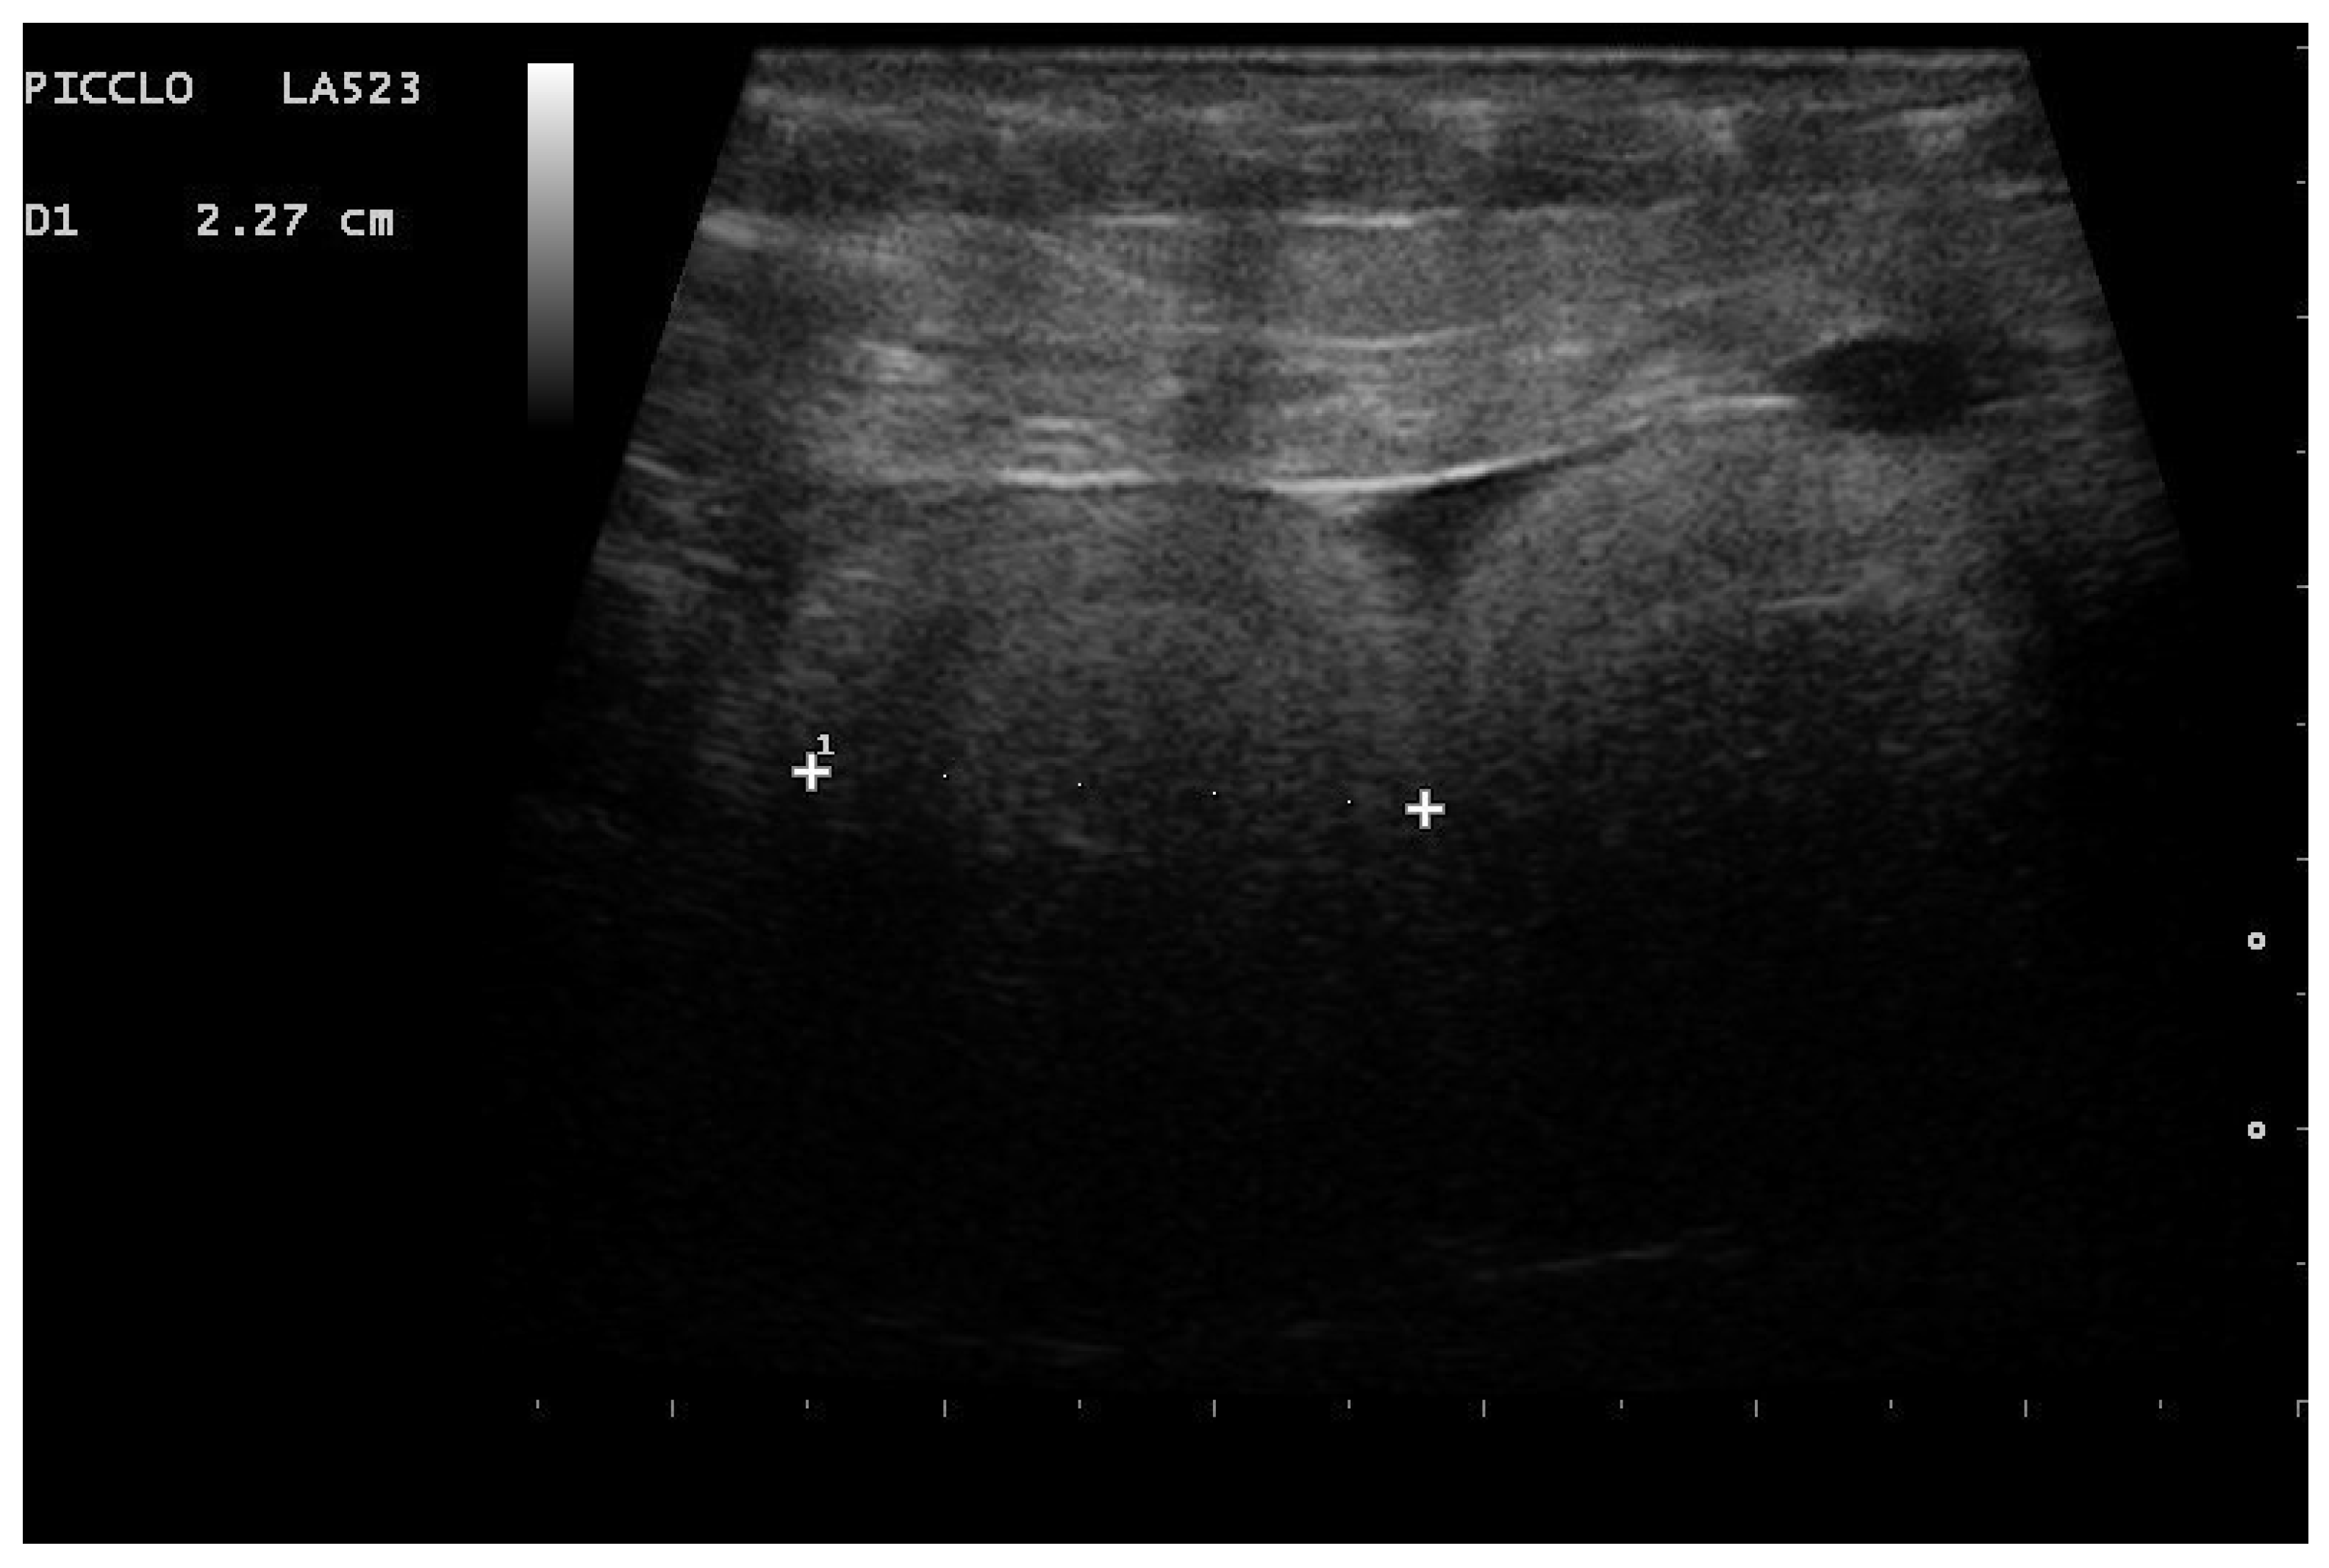

- Garcia, V.C.; Almeida-Santos, S.M. Reproductive cycles of neotropical boid snakes evaluated by ultrasound. Zoo Biol. 2021, 1–10. [Google Scholar] [CrossRef]

- Isaza, R.; Ackerman, N.; Jacobson, E.R. Ultrasound imaging of the coelomic structures in the Boa constrictor (Boa constrictor). Vet. Radiol. Ultrasound 1993, 34, 445–450. [Google Scholar] [CrossRef]